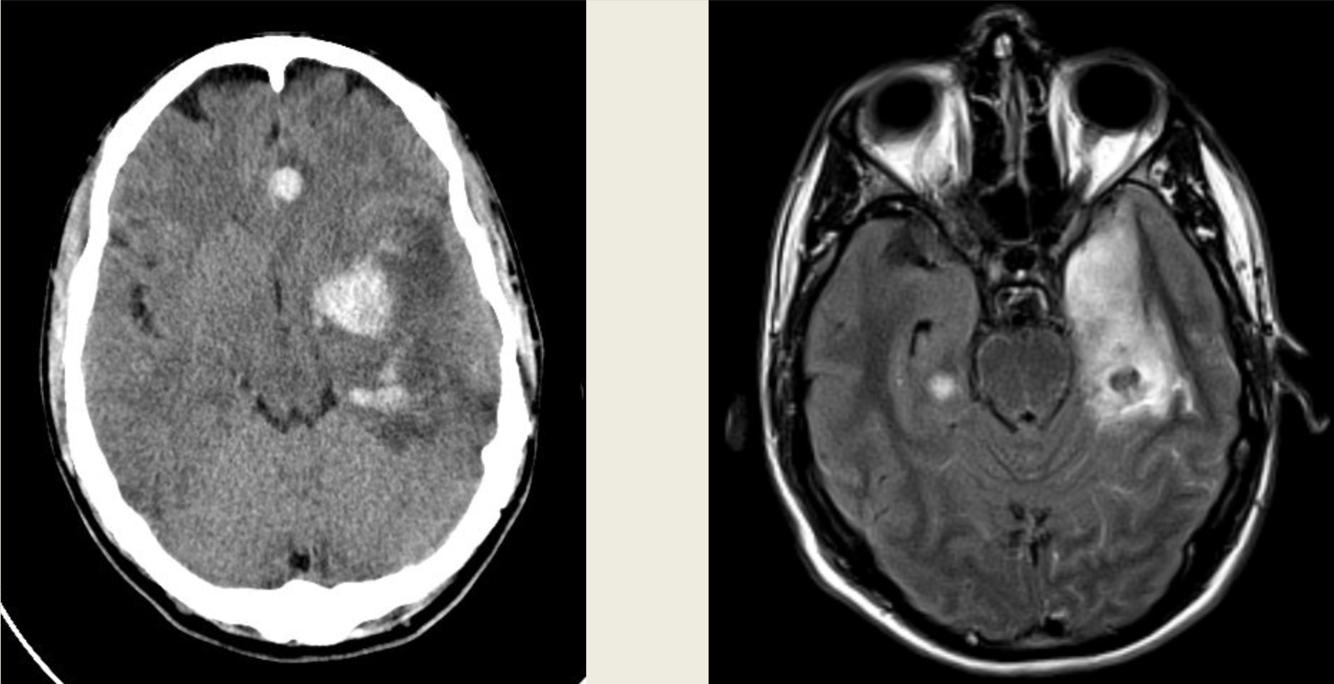

48 y/o M admitted for ETOH withdrawal, became encephalopathic and parkinsonized in hospital.

Central pontine and extrapontine myelinolysis